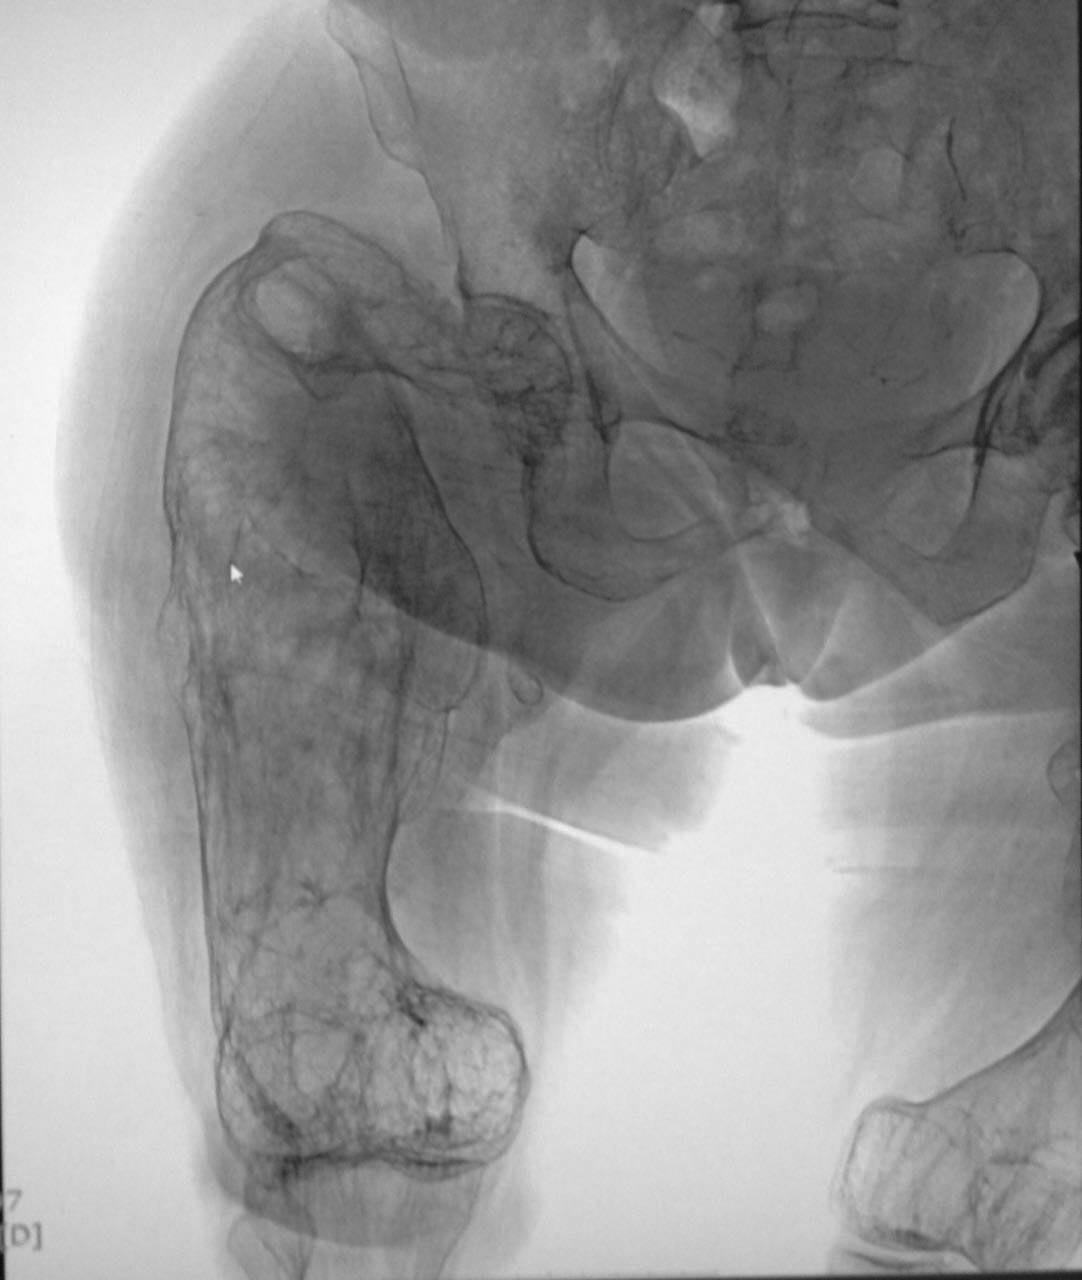

Пациентка Н. 1940 года рождения поступила в стационар по экстренным

показаниям с предварительным диагнозом: Закрытый перелом шейки правой

бедренной кости на фоне выраженного дегенеративно-дистрофического

изменения правой бедренной кости. Выраженный болевой синдром.

Стенокардия напряжения ФК 2. Гипертоническая болезнь 3 ст.,

риск 4. ХСН 1. Со слов упала с высоты своего роста за 2 дня до поступления.

Из анамнеза: в детстве была обычным ребенком, развитие по возрасту.

Работала полировщицей на заводе, работа связана с вибрацией. Со слов

пациентки появились боли области бедер и ТБС с 1984г, далее

присоединились ограничения в движениях тазобедренных суставах. в 2006,

2007, 2009гг патологические переломы бедренных костей на уровнях с/3 и

шейки. Перенесенные заболевания: гипертиреоз.

Уважаемы коллеги, помогите определиться сопутствующей патологией. С

выбором тактики дальнейшего лечения.

На данный момент придерживаемся консервативного метода лечения.